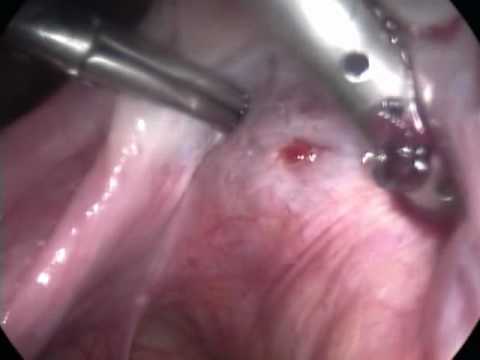

• HISTEROSCOPIA (P.O.): Avaliação endometrial + biopsia

Histeroscopia: diagnostico e tratamento: polipectomia